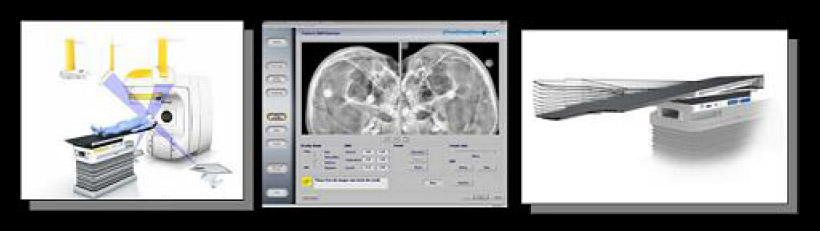

2.5mm マイクロマルチリーフ HD120mMLC

ビーム射出⼝のしぼりは2.5mm刻みで微細照射野から22 x 40cmの⼤照射野までほぼ全ての治療状況を可能とします。

(中央8cmが2.5mm幅。上下7cmが5mm幅合計120枚のリーフが微⼩な精密照射野から⼤照射野までをカバーする)

ExacTrac X-Ray/Robotic 6D couch

治療機本体とは独⽴して、天井、床に固定・埋設した⾚外線カメラと2⽅向からのX線撮影の2つの位置決め機構により、体表および⾻格のコンピューター計画時と位置ずれ量を正確に算出します。誤差の算出精度は0.1mm。そして、位置ずれ量に応じて、ロボット寝台が⾃動的に移動して修正します。

このシステムにより、⾃動かつ⾼精度に位置補正が⾏え、治療時間も短くできます。

Eclipse Ver. 13.6(バリアン社)/ iPlan Ver. 4.5.5(ブレインラボ社)

回転IMRT(Rapid Arc)計画も可能